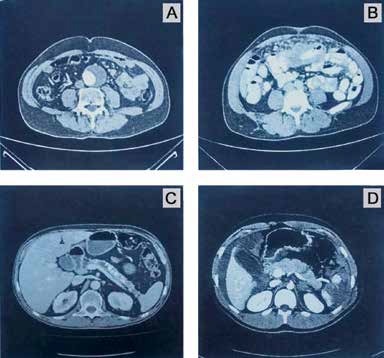

1 – Adolescente masculino de 16 anos de idade, trazido ao pronto-socorro de hospital terciário pelo Serviço de Resgate, foi vítima de queda de bicicleta após colisão em alta velocidade contra anteparo fixo. Paciente relata ter traumatizado a região superior do abdome contra o guidão da bicicleta e refere intensa dor no local. Apresenta ainda trauma craniano, sem perda de consciência, porém refere cefaleia intensa. Nega vômitos. Dados colhidos pela equipe do resgate no local do acidente: Pulso = 112 bpm; pressão arterial = 130 x 90 mmHg; frequência respiratória = 16 irpm; saturação de oxigênio 97% em ar ambiente. Tempo entre acidente e admissão hospitalar: 30 minutos. Na avaliação no pronto- socorro: A: Vias aéreas pérvias, com colar cervical. B: Murmúrios vesiculares presentes bilateralmente; expansibilidade simétrica; tórax indolor à palpação; sem crepitações; FR = 16 irpm; saturação de O2 98% em ar ambiente. C: Pulso = 108 bpm; pressão arterial = 120 x 70 mmHg; sem sangramento visível. Abdome doloroso à palpação em epigástrio e mesogástrio, onde se evidenciam equimose e escoriação. Toque retal sem alterações, diurese clara. D: Escala de Coma de Glasgow = 15; pupilas isocóricas e fotorreagentes. E: Sem outras alterações. Realizada expansão volêmica com 2.000 ml de soro fisiológico e analgesia. Após essas medidas, o paciente apresenta frequência cardíaca de 86 bpm e pressão arterial de 120 x 70 mmHg. Marque a letra correspondente à imagem com as lesões mais compatíveis com o mecanismo deste trauma:

Dentre as tomografias computadorizadas de abdome demonstradas, qual é a mais compatível com o caso apresentado? É realmente isso que o enunciado deseja saber. Fica aqui uma dica: quando avaliamos uma questão com imagem de exames complementares radiológicos, antes de “partirmos direto” para a imagem propriamente dita, é fundamental que leiamos com muito cuidado a história clínica descrita. Nosso paciente foi vítima de contusão abdominal, consequência de impacto de bicicleta contra um anteparo fixo, na realidade houve choque do abdome superior contra o guidão da bicicleta. De objetivo na avaliação inicial do paciente: encontra-se hemodinamicamente estável, taquicárdico e com dor a palpação em mesogástrio e epigástrio, onde há sinais de escoriações e equimoses. A taquicardia pode representar tanto perda volêmica discreta, quanto ser ocasionada por dor. Recebeu 2.000 ml de cristaloides e analgesia. Manteve pressão arterial estável e houve redução da frequência cardíaca. Agora, vamos lá: na imagem A nós temos um aneurisma de aorta abdominal com trombo mural (seta amarela) como principal achado; na imagem B chama a atenção alça espessada (seta amarela); e na imagem C reparem que há múltiplas calcificações pancreáticas (setas amarelas), o que denota uma pancreatite crônica, sem dúvida alguma. A imagem D é compatível com a história descrita. Vejam uma imagem bastante hipodensa em topografia de baço, sem definição de cápsula esplênica, onde há também extravasamento de contraste (alterações presentes em setas verdes), ou seja, temos um parênquima esplênico bastante comprometido (pulverizado?). As setas amarelas correspondem ao líquido livre em cavidade, que em uma topografia mais superior se infiltra por sobre o fígado também (não é hematoma hepático!). Até aí entendemos esses achados – o trauma esplênico foi o responsável por esse líquido livre (na realidade um hemoperitônio). A taquicardia pode realmente ter representado essa discreta perda volêmica (hemorragia classe I). Além destes achados, temos uma imagem hipodensa linear em corpo de pâncreas (seta vermelha), o que traduz uma laceração corpocaudal pancreática. O mecanismo dessa lesão foi a compressão do corpo do pâncreas entre o guidão da bicicleta e a coluna vertebral. Podemos concluir, sobretudo com essa lesão pancreática, que o paciente foi vítima de uma contusão abdominal realmente intensa. Observamos também nessa tomografia computadorizada imagem de vesícula biliar distendida (seta branca), o que não tem importância alguma para o caso (jejum prolongado?).